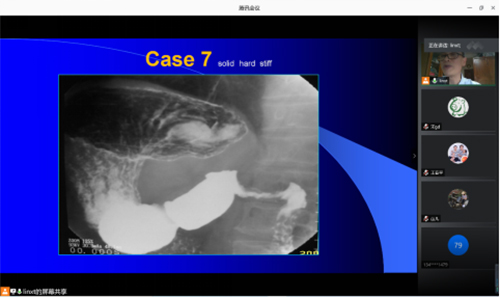

在常态化抗击疫情的现在,为更好的对医学影像科规范化培训学员进行专业教育,医学影像科在开展每日早阅片的同时,做好平时工作及相关专业培训邀请,每周一、周四晚上定期邀请科室专家进行线上相关专业知识讲座,每次线上讲座都吸引了众多学员及科室工作人员进行观看、学习。医学影像科作为省内专业的住院医师培训基地,科室通过线上+线下相结合的方式有效保障了正常教学培训活动的开展。

科室林祥涛教授进行胃肠造影检查的相关培训